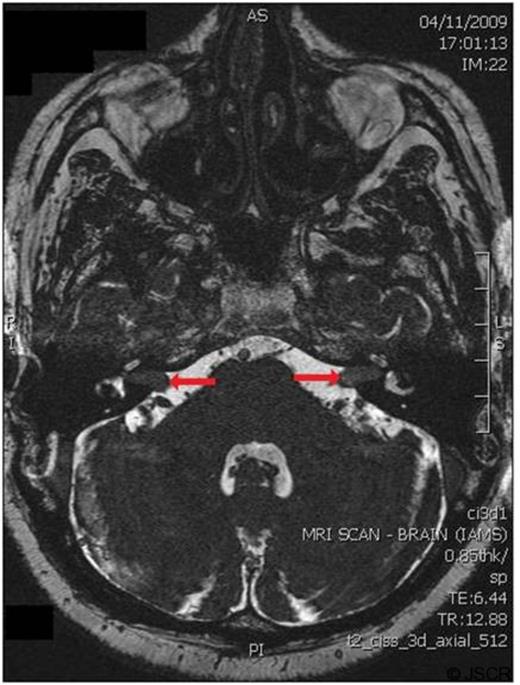

He developed a sudden loss of hearing which was initially unilateral but became bilateral. The deafness was accompanied by dizziness, but there was no other detectable focal neurology. Magnetic resonance imaging identified bilateral lesions, each approximately 2 centimetres in diameter, at the internal auditory meatus (figure 2), consistent with a radiological diagnosis of bilateral acoustic neuromas.

Magnetic resonance imaging at the level of the internal auditory meatus, showing bilateral mass lesions (highlighted by arrows)